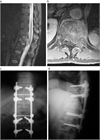

1. がんの既往のある患者が脊椎に痛みを訴えた場合、転移性脊椎腫瘍を念頭に置くことが推奨される(推奨度1)

1. 転移性脊椎腫瘍を疑った場合、全身の造影CTを撮影することが推奨される(推奨度1)

1. 転移性脊椎腫瘍と診断した場合、余命を評価することが推奨される(推奨度1)